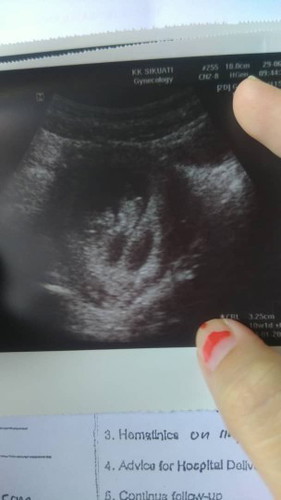

Scan 10 week

Doctor dapat dua kantung tapi doc cakap kantung satu masi kosong d sngka cyst tapi sy xpercya firasat sy kuat dua2 ada#bantusharing #pleasehelp #seriusnanya

Puan scan dekat mne?? Normally 10 weeks dah boleh dgr jantung baby.. sye start dengar jantung baby masa baby 8 weeks, masa tu xsedap bdn n suspect pregnant.. baby pon dah nmpak jelas mse first scan.. cube tunggu dlu seminggu dan repeat scan.. buat mse skrg bykkn berehat dan mkn yg berkhasiat dan bykkn mkn buah

Baca lagiHai sis scan atas ke bwh ni? Scan bwh sepatutnya lebih jelas. Nanti ada repeat scan lagi kan sis? Saya doakan yg baik-baik ye. Saya masa 6w4d dh nmpk baby & dgr heart beat scan atas & bwh dgn doktor pakar O & G.

nanti sis ulang scan lagi seminggu.